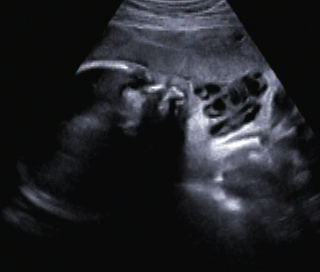

Ein zunächst durchgeführtes CTG war unauffällig. Im Rahmen der sonografischen Untersuchung zeigte sich der Fötus soweit beurteilbar zeitgerecht entwickelt. Dennoch konnte ein Anhydramnion festgestellt werden(Abb. 1, 2), weshalb auch kein fetales Gesicht darstellbar war (Abb. 3).